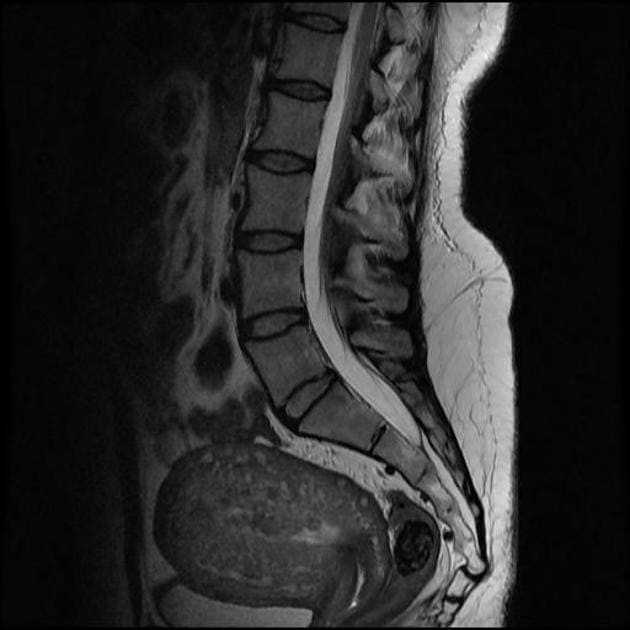

- Дополнительные методы исследования, такие как рентген или МРТ, могут быть назначены для получения более детальной информации о повреждении.

Важно отметить, что рентгенологическое исследование не является единственным методом диагностики повреждений копчика после вывиха. Оно часто дополняется другими методами, такими как магнитно-резонансная томография или компьютерная томография, которые позволяют получить дополнительную информацию о состоянии окружающих тканей и детализацию повреждений кости и сустава.